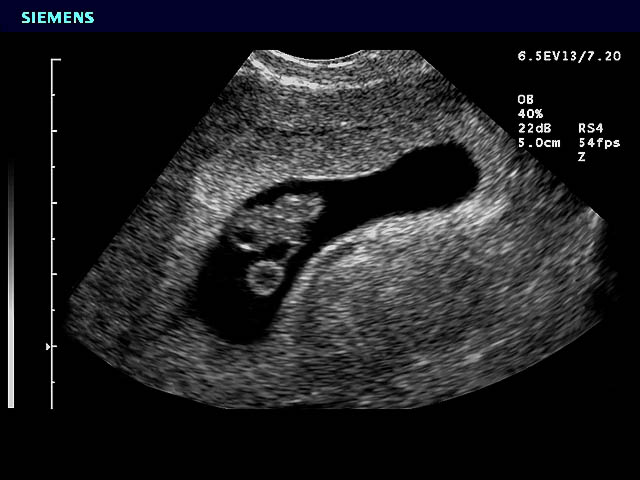

Rasa mual dan muntah ini muncul saat kandungan berusia 1 minggu bahkan ada yang sampai 3 minggu. Usg usia 7 minggu baru nampak kantung kehamilan. Selain dua kondisi gambaran hasil usg kehamilan 5 minggu yang ditunjukan diatas beberapa ibu hamil terkadang sudah dapat terlihat adanya janin di dalam kantung kehamilan. Usia kehamilan 8w belum tampak janin. Laporan studi kasus dengan judul manajemen asuhan kebidanan pada ibu hamil nya g1p0a0h0 usia kehamilan 6 7 minggu di bps lusi meilidayeni ssit air salo petok kabupaten pasaman timur tanggal 17 19 oktober 2014 telah diseminarkan dan dipertahankan dihadapan tim penguji laporan studi kasus prodi diii kebidanan stikes mercubaktijaya padang. Bayi dalam kandungan anda juga sedang membesar dengan cepat dan kini dia sudah berukuran kira kira 10mm panjang ii sebesar saiz buah beri biru.

Dari minggu ke 11 hingga ke 20 separuh perjalanan kehamilan ini bayi anda akan bertambah panjang hingga tiga kali lipat dan beratnya juga bertambah sebesar 30 kali lipat. Di minggu ke 5 ini mungkin mom sudah mulai menyadari kalau mom sedang hamil karena terlambat datang bulan. Pusing adalah ciri awal kehamilan saat usianya 1 minggu atau hingga 3 minggu tergantung kondisi tubuh ibu. Namun perlahan tapi pasti perkembangan proporsi tubuhnya akan berlanjut pada minggu minggu berikutnya dan bayi anda akan semakin terlihat seperti manusia mungil. Contoh askeb pada ibu hamil normal 7122016 askeb bidan contoh askeb ibu hamil comment asuhan kebidanan ibu hamil normal tm ii. Usia 7 minggu kehamilan baru terlihat kantung hamil saja hamil kembar tapi satu kantong help me bund.

Membaca hasil usg ni bund usia 8 minggu detak jantung belum terlihat. Kontur mata hidung mulut telinga dan beberapa bagian lain di wajah bayi akan mulai terbentuk minggu ini. Kadar hormon yang berubah saat hamil menyebabkan rasa pedih pada bagian perut sehingga menimbulkan rasa mual bahkan hingga muntah. Perkembangan bayi dalam kandungan 7 minggu perkembangan fetus bayi ibu hamil 7 minggu hamil minggu ketujuh tanda hamil usia 7 minggu kondisi keadaan ibu hamil umur kandungan minggu ke 7 bila tarikh mengandung gambar bayi janin 7 minggu tips menjaga kehamilan ibu mengandung saiz bayi usia kehamilan 7 minggu sebesar biji kacang kuda cara baca alat ujian hamil upt urine pregnancy test. Pentingnya pemeriksaan kandungan dan usg rutin untuk mendeteksi dini resiko komplikasi dan penyakit kehamilan memantau perkembangan ibu dan janin serta menurunkan resiko kematian ibu hamil dan janin dalam kandungan atau setelah lahir.